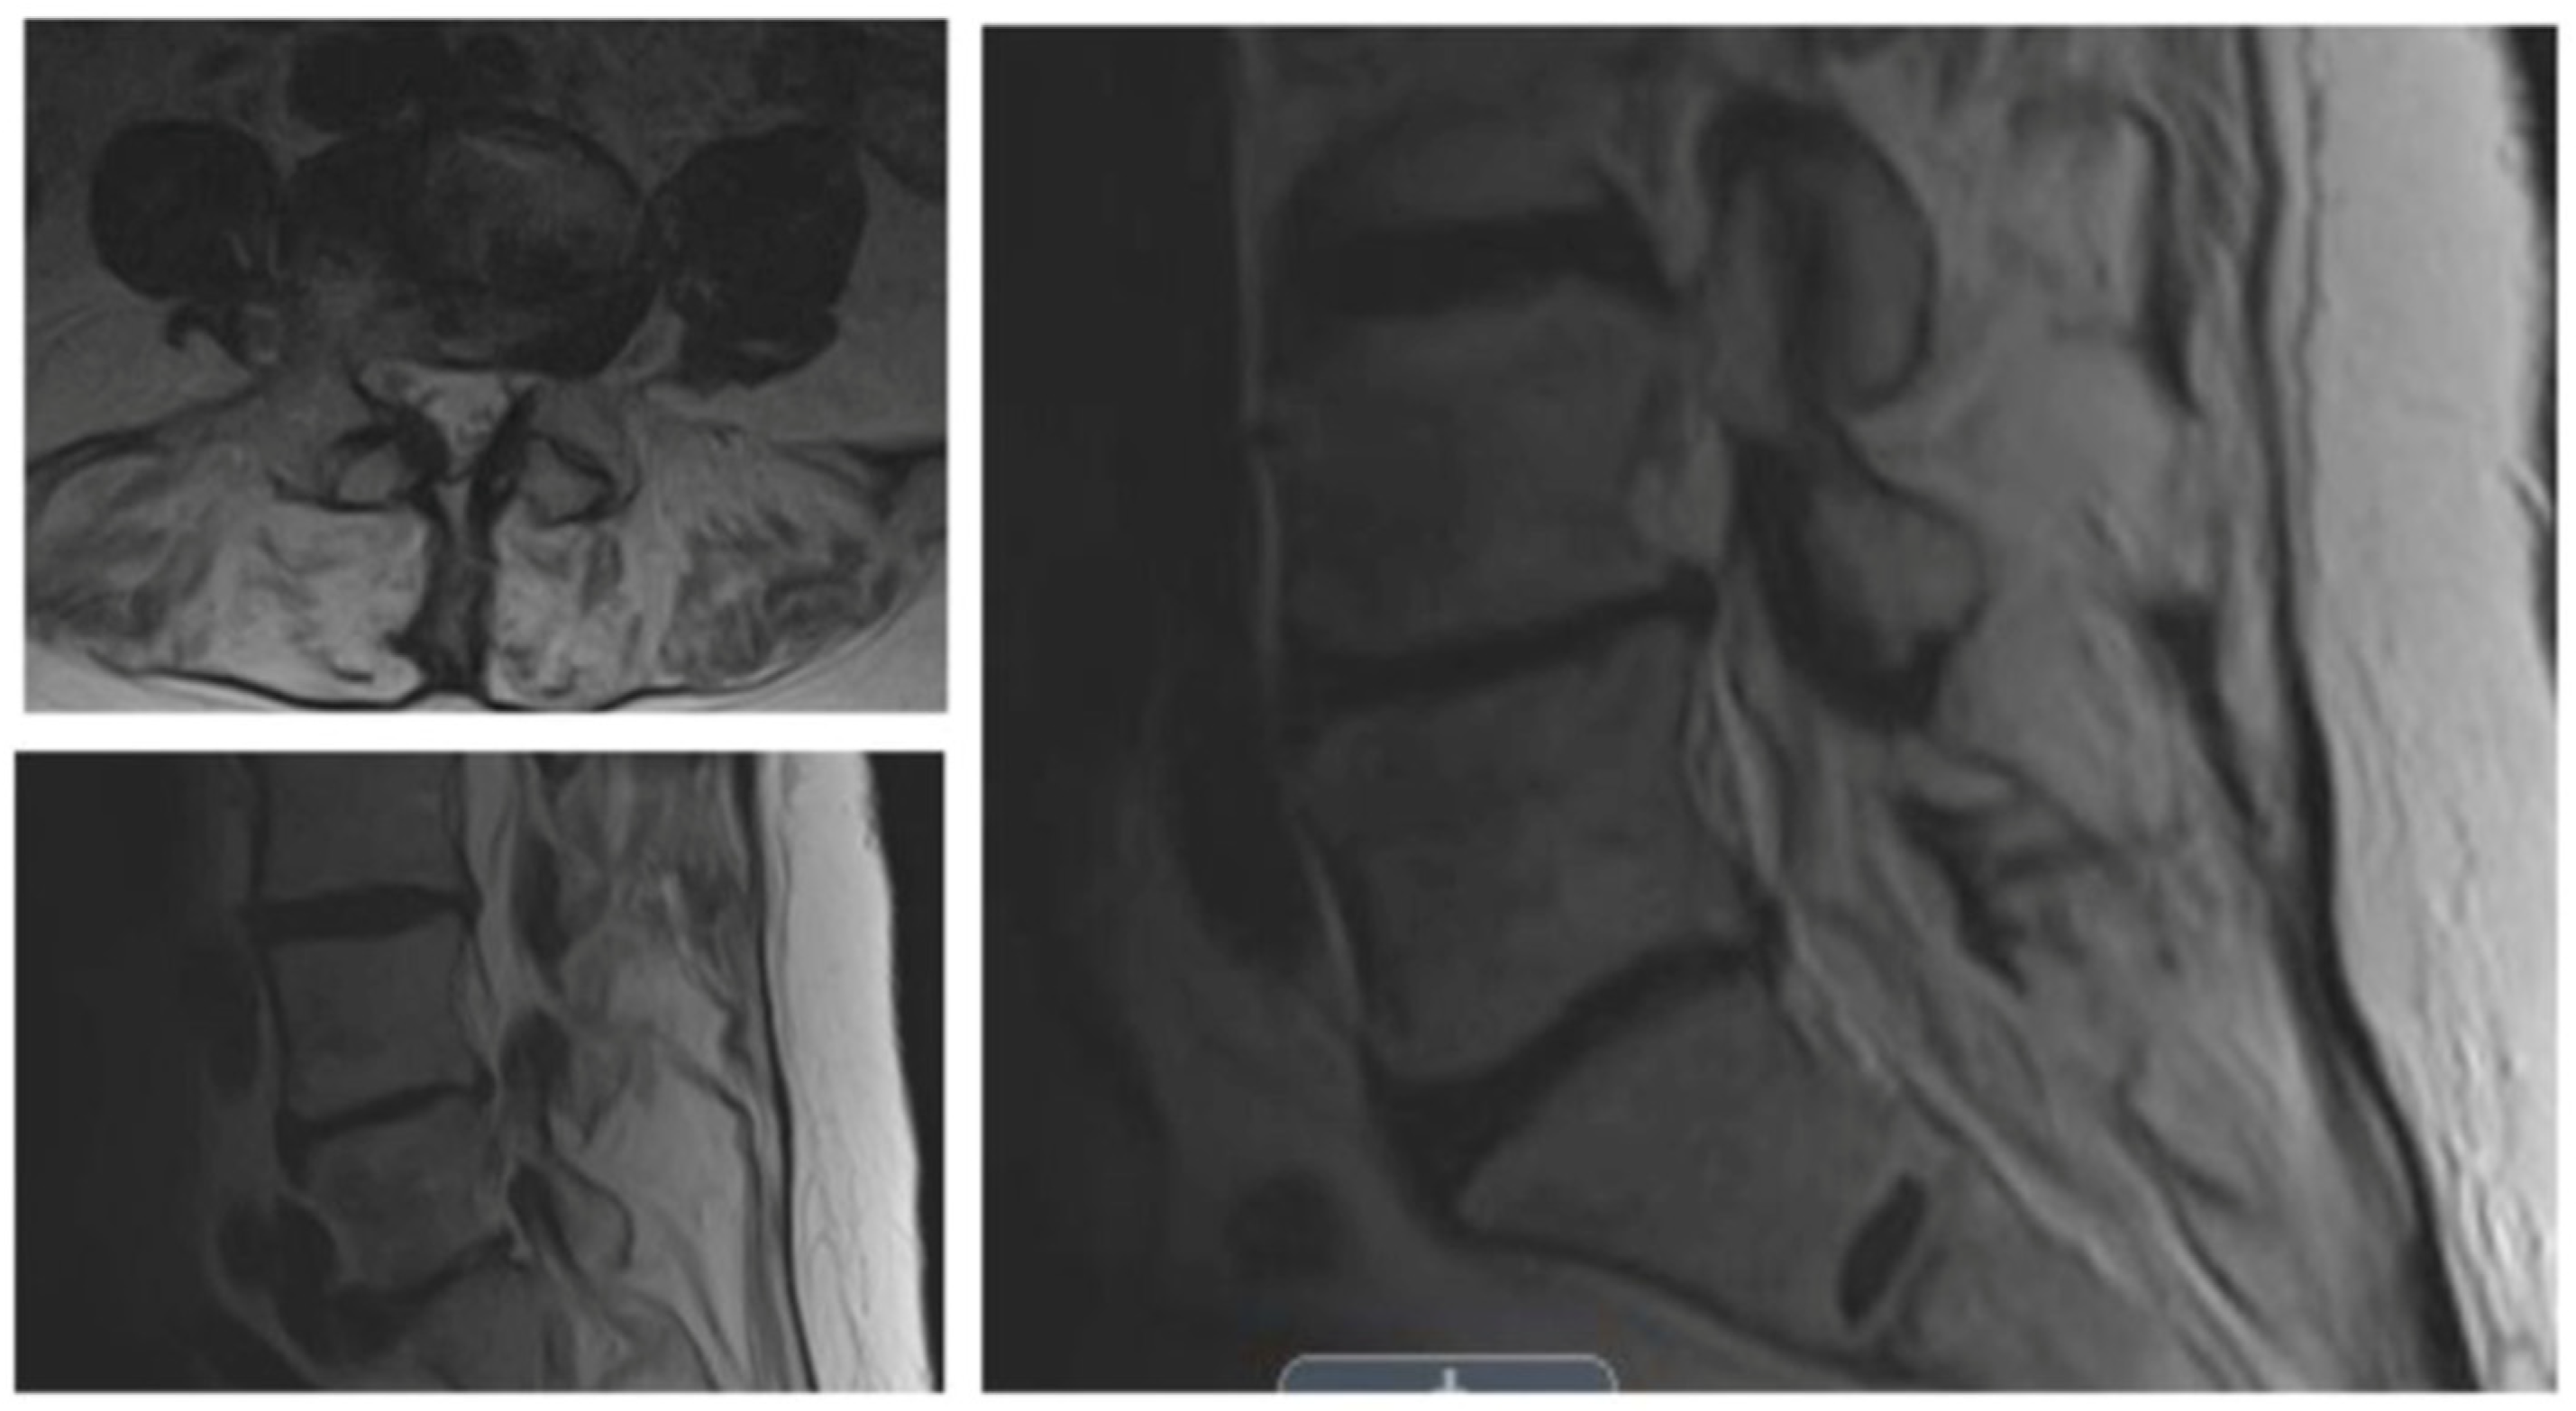

The survey was posted on TypeForm (http://www.typeform.com; accessed on 1 May 2022). The authors contacted 210 surgeons to request their participation. The survey was started by 82 endoscopic spine surgeons and completed by 30. It concluded on 15 June 2022. Thus, the completion rate was 36.6%. In the survey app, surgeons could see the comparator CPT® code number, its verbal description by the AMA, and the wRVUs assigned by CMS. As a measure of workload, surgeons were asked to select a CPT® code from the list of comparator codes that best equated to the work involved when performing an endoscopic surgery billed under CPT® code 62380. The surveyed procedure was illustrated in a clinical vignette of a 66-year-old female patient with a 6-month history of progressive leg pain/claudication with some back pain (visual analog scale (VAS) for back pain > 50/100; Oswestry Disability Index (ODI) > 40%) unresponsive to conservative treatments (Figure 1). MRI demonstrated a moderate-to-severe spinal lateral recess and foraminal stenosis at a single level. Flexion/extension radiographs revealed instability (<3 mm) without spondylolisthesis. It is essential to note that the wRVUs of the surveyed procedure continue to be unavailable on the CMS websites, and thus, were not provided as part of the survey.

Figure 1. The patient vignette given to responding surgeons described a 66-year-old female with a 6-month history of progressive leg and back pain consistent with neurogenic claudication unresponsive to conservative treatments. The patient consistently rated her symptoms > 50/100 on the visual analog scale (VAS) for back pain, and her associated disability > 40% with the Oswestry Disability Index (ODI).